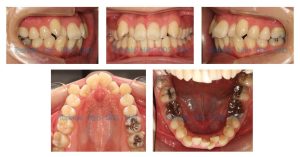

初診時27才の女性、上下前歯の叢生と顎関節の雑音を主訴に来院されました。

Angle Class I crowding

Bimaxillary protrusion

Flared out of A/A incisors

Skeletal II (ANB 8.6)

ALD: -8.0/-7.0 mm

OJ/OB: 5.0/4.0 mm

Midline: A/A coincident with facial midline

上記診断のもと、右上4、左上4、右下5、左下5を抜歯し、動的矯正治療を開始しました。